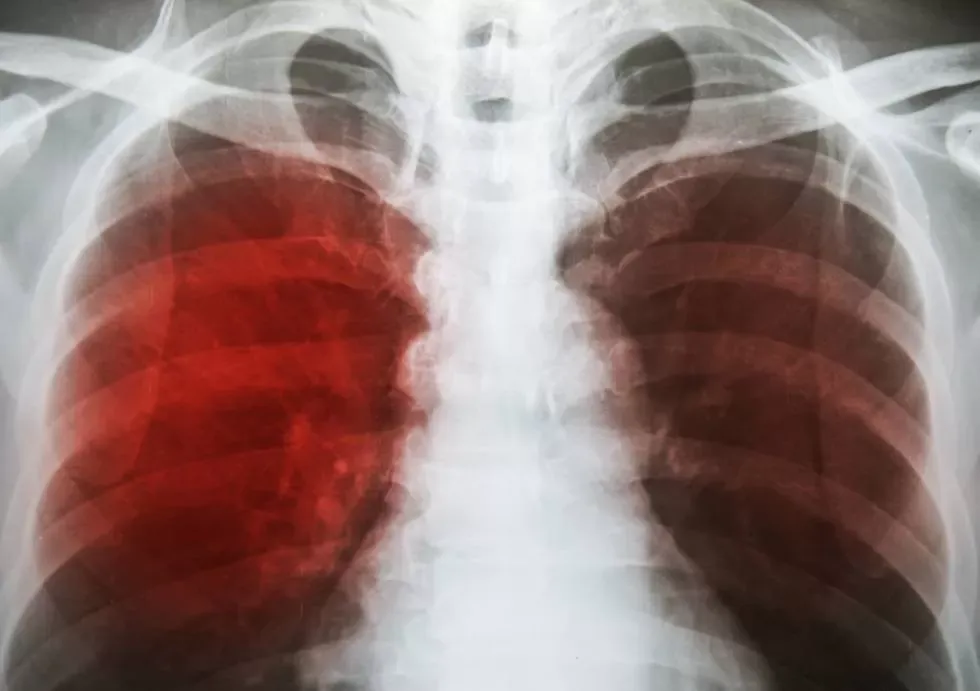

"La Covid y la tuberculosis tienen algo muy particular: ambos comienzan con algo intenso, con el desgano, con la fiebre, con un paciente que tose, con un paciente que se vuelve tosedor, con un paciente en malas condiciones respiratorias".